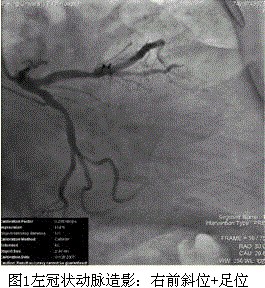

问题 患者女,74岁,主因“间断胸痛20余年,加重2个月”入院。5年前行冠状动脉造影检查示右冠状动脉完全闭塞,前降支弥漫病变,于前降支近中段植入支架3枚。此后患者仍偶有胸痛发作。2个月前,开始出现活动中胸痛,以饱餐后为著,且症状逐渐加重,活动耐量逐渐降低。既往:原发性高血压史10余年,糖尿病史4年。入院查体:Bp 140/70 mmHg。双肺呼吸音清,未闻及干、湿啰音。心界不大,心律不齐,可闻及期前收缩约5次/min。肝、脾肋下未及。双踝部轻度可凹性水肿。ECG检查:房性期前收缩二联律。 对于此患者适当的治疗策略是(提示 入院后UCG检查:左心室肥厚,舒张功能减低;左心房扩大;LVEF:61%。主要实验室检查结果:CK-MB 0.6 ng/ml,cTnI 0.01ng/ml,Scr 133 μmol/L。冠状动脉造影结果(图1、2):左冠状动脉:LAD中段原支架内狭窄50%60%,LCX近段狭窄70%80%;右冠状动脉:近段弥漫病变,自中段完全闭塞。